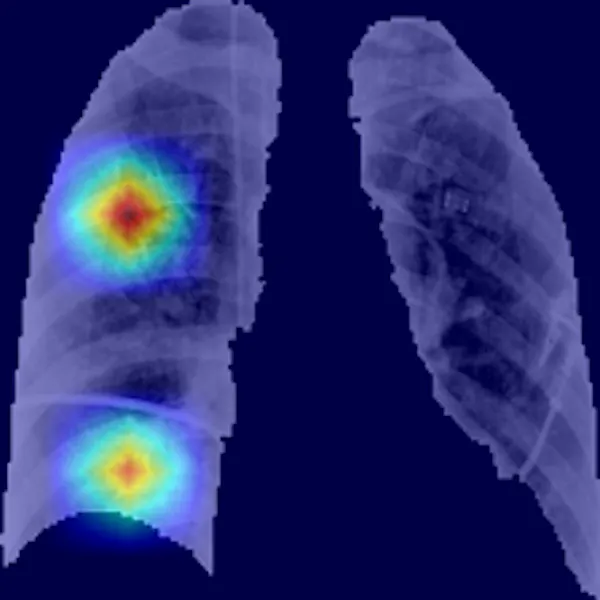

Apoyados en la capacidad que los modelos basados en inteligencia artificial tienen para obtener información que incluso está oculta al ojo humano, investigadores de la Universidad de Antioquia, la Johns Hopkins University y la Universidad Politécnica de Madrid hemos desarrollado un prototipo de sistema computarizado de diagnóstico de la covid-19 y de evaluación del grado de afectación de los pulmones a partir de imágenes radiológicas de tórax. Dicho sistema ha sido desplegado en un prototipo de aplicación en la nube siguiendo un modelo de software como servicio.

La herramienta proporciona un método objetivo complementario, mínimamente invasivo para el diagnóstico, que evalúa el grado de afectación por la covid-19. Alcanza una precisión por encima del 90%, superior incluso a la alcanzada por los expertos en radiología. Además, proporciona evidencias con capacidad diagnóstica en estadios incipientes de la enfermedad (los cinco primeros días).

La herramienta también identifica el área de mayor afectación y permite cuantificar de forma objetiva lo extenso de la infección. Sin olvidar que reduce significativamente el tiempo dedicado por los expertos en radiología a la evaluación de cada paciente.